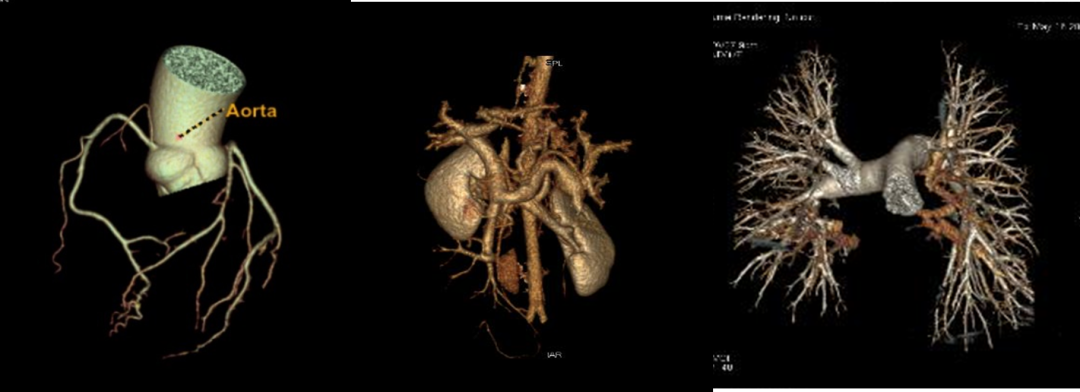

扫描速度快,全身检查只需10秒钟;对于血管性疾病,可发现更细小的血管分支;不受心率、呼吸限制,一次心跳即可完成冠脉CT检查;噪音极小;单能量成像,更加准确的绝对CT值;低KeV成像,更高的组织对比度;多参数功能成像,可进行多种基物质浓度及有效原子序数测定。

1.单能量图像:能谱CT可提高图像质量,显示病灶内部特征,临床可用于所有血管检查及增强扫描。

2.物质定量和分离:实现定量分析,临床中常用的碘基物质图像可评估血管及强化程度。